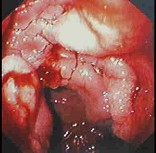

男性,50岁。消瘦、乏力半年,间断性上腹胀痛伴黑便2周。发育正常,体形消瘦,贫血外貌,皮肤无黄染,腹平坦,腹肌软,上腹偏右压痛,肝脾肋缘下未触及。低张气钡双重造影示十二指肠降段肠壁僵硬,蠕动消失,肠腔不规则狭窄。胃镜检查如下图,下列正确的是()。

A:十二指肠腺癌可能大

B:卓-艾综合征可能大

C:该病可导致黄疸

D:该病以中年人多见

E:该病首选手术治疗,无手术指征者可考虑放、化疗